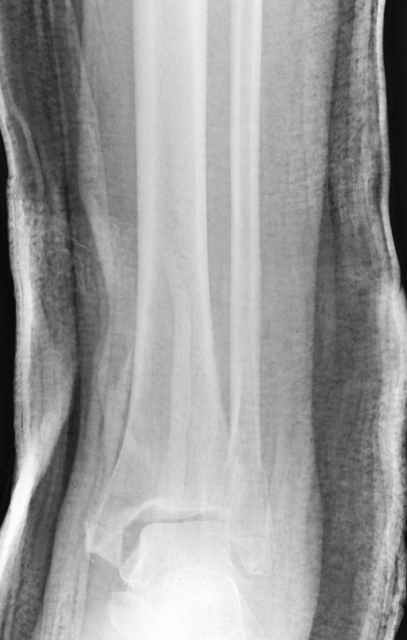

Pilon fracture:

-Появляется ориентир и остов, на чем можно строить восстановление, почему сперва малоберцовую, впервые обьяснили и описали (Pylon type and Ankle fractures) в середине 50х Rienau и Gay.

Восстановливая длину и ротацию малоберцовой кости, затем относительно легче произвести реставрацию остальных элементов перелома дистального эпиметафиза болшеберцовой кости.

где исследования на трупах показали, что малоберцовая кость участвует в стабильности голеностопного сустава, поддерживая наклон тарана (talar tilt) за счет связок. После ознакомления работой Ramsey в ортопедию ввели термин "при переломах голеностопного сустава смещенная

таранная кость следует за малоберцовой костью" т.е. связка не рвется, а тянет таран за собой, поэтому восстановление малоберцовой кости в

первую очередь, затем остальных элементов - стал классическим при лечении данной патолгии. Латеральная колонна (столб), дистальный

конец малоберцевой кости, к нему прикрепляется латеральный суставной фрагмент дистального эпиметафиза большеберцовой кости (как на снимке)

и таранная кость, которые при репозиции малоберцовой кости репонируются автоматически.

Дистракция в аппарате или на вытяжение результат - лигаментотаксис, посмотреть бы, как сегодня расположены отломки.